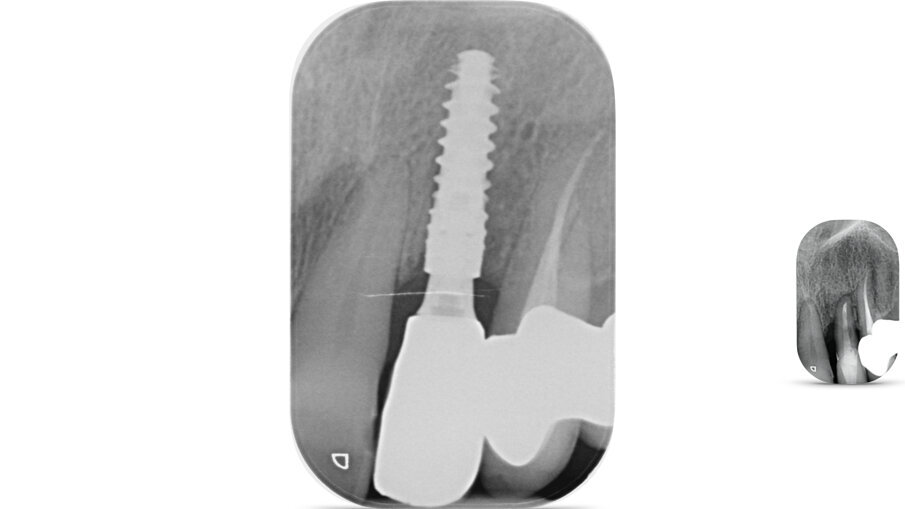

È stato inserito un impianto Straumann BLX 3.75 mm di diametro per 12 mm di lunghezza, con superficie SLActive seguendo l’asse protesico ideale (Figg. 4, 5). Avendo conseguito una stabilità primaria eccedente i 35 N/cm è stato realizzato un restauro provvisorio avvitato in composito su componente in Titanio da provvisori. Nonostante una sostanziale congruità della forma del provvisorio con la parte superficiale dell’alveolo, è stata utilizzata una matrice dermica suina (Botiss Mucoderm) allo scopo di sigillare il gap presente tra provvisorio e bordo mucoso dell’alveolo. Tale matrice, opportunamente sagomata e forata in modo da essere stabilizzata dal provvisorio stesso, è stata posizionata in modo da non rimanere esposta al cavo orale. Non sono state necessarie suture (Figg. 6-8).

Fig. 5_Rx periapicale post-impianto.